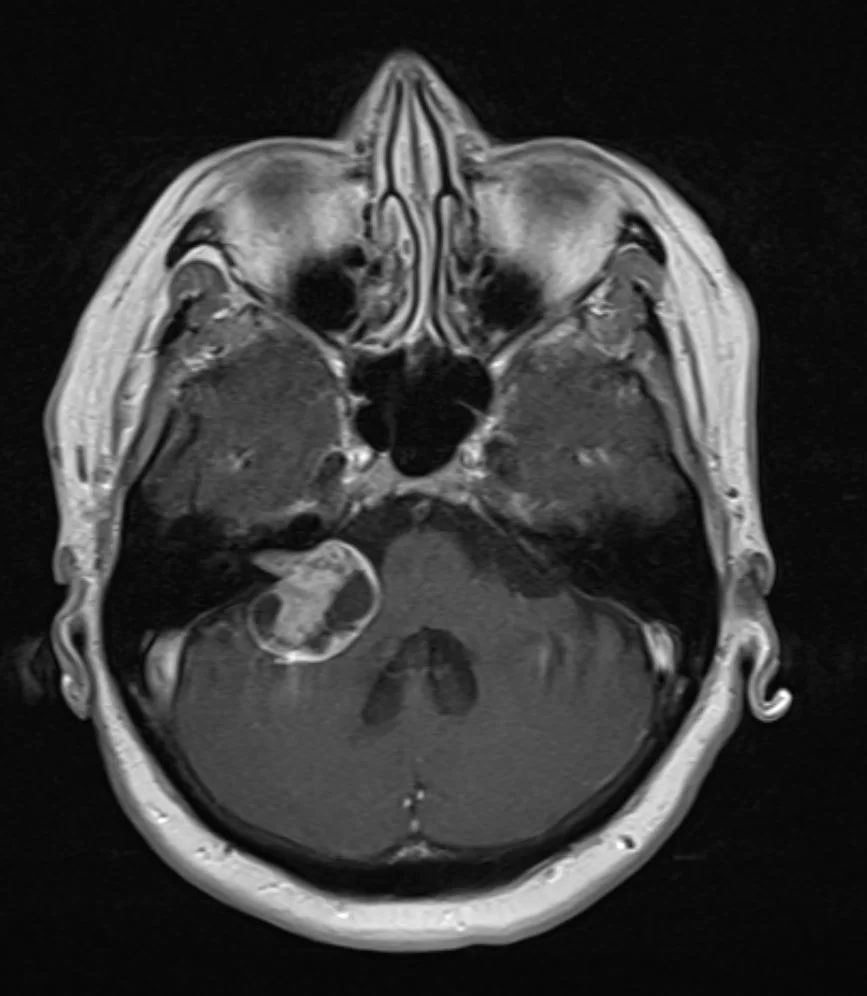

Η μαγνητική τομογραφία εγκεφάλου ανέδειξε χωροκατακτητική εξεργασία στη δεξιά γεφυροπαρεγκεφαλιδική γωνία συμβατή με ακουστικό νευρίνωμα (αιθουσαίο σβάννωμα) και πίεση επί του στελέχους (Koos IV).

Η ασθενής υπεβλήθη σε δεξιά οπισθοσιγμοειδική κρανιοτομία και ολική αφαίρεση της βλάβης.

Τα ακουστικά νευρινώματα είναι χειρουργικά απαιτητικοί όγκοι, λόγω της εγγύτητάς τους με πολλά εγκεφαλικά νεύρα και κυρίως με το προσωπικό νεύρο. Στο συγκεκριμένο περιστατικό υπήρχε πίεση επί του στελέχους και ο όγκος –αν και καλοήθης- ήταν αρκετά μεγάλος, οπότε η ένδειξη για χειρουργείο ήταν σαφής.